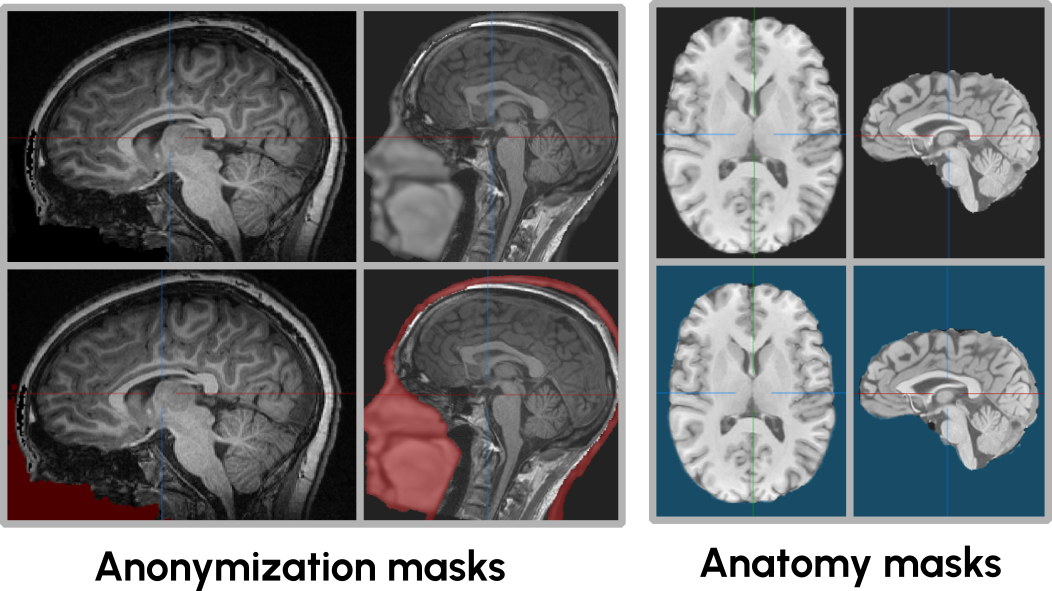

With these 114k 3D images, self-supervised pre-training becomes feasible. However, due to the nature of these scans capturing the head-and-neck region, many structural images have undergone an anonymization process to ensure participant privacy. Common anonymization techniques include defacing, blurring of everything but the brain or brain extraction, see Figure 2. These augmented regions can interfere with reconstruction-based SSL methods, potentially penalizing models for attempting to reconstruct plausible anatomical features in anonymized regions. To allow taking these regions into account complementary masks to the images are mandatory. Unfortunately, not all of the 700 datasets provide these masks, despite applying some sort of anonymization.

Refer to caption

Figure 2: Structural images are often defaced, have the face blurred or have been brain-extracted to assure the privacy of the participants, which can potentially harm reconstruction based SSL methods. Anonymization and anatomy masks are provided to allow taking this into account during method development.

To address this issue, we generate associated anonymization masks and anatomy masks for cases where these are not provided (Figure 2 bottom). The anonymization mask identifies areas where anatomical structures have been artificially modified or removed and where no loss should be calculated, whereas anatomy masks indicate where relevant foreground is present allowing to avoid sampling non-empty patches which may speed up the convergence of the pre-training methods. Both of these masks are created using a recently published defacing and anonymization tool222Code available here..